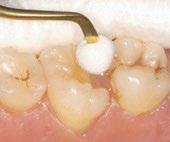

With the universal composite BRILLIANT EverGlow

highly aesthetic and long-lasting restorations can be achieved effortlessly.

Exceptional polishability and long-lasting brilliance

Aesthetic single-shade restorations

Versatile shade system with three translucency levels

Excellent sculptability and smooth consistency

Good wettability with minimal stickiness to the instrument

Initial situation: discoloration Opaque shade applied

HIGHLY AESTHETIC RESULTS Final restoration